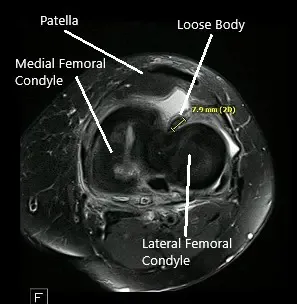

Una resonancia magnética de la rodilla izquierda sugirió osteoartrosis con pérdida de cartílago de alto grado en el compartimento medial y pérdida de cartílago de alto grado cartílago trocleare central con pérdida condral de bajo grado cartílago rotuliano. Gran desgarro radial del cuerno posterior del menisco medial , que está extruido periféricamente. Hay un cuerpo suelto en la parte profunda de la almohadilla grasa de Hoffa que mide 4 mm x 8 mm.

Resonancia magnética de la rodilla izquierda que muestra secciones axial y coronal.